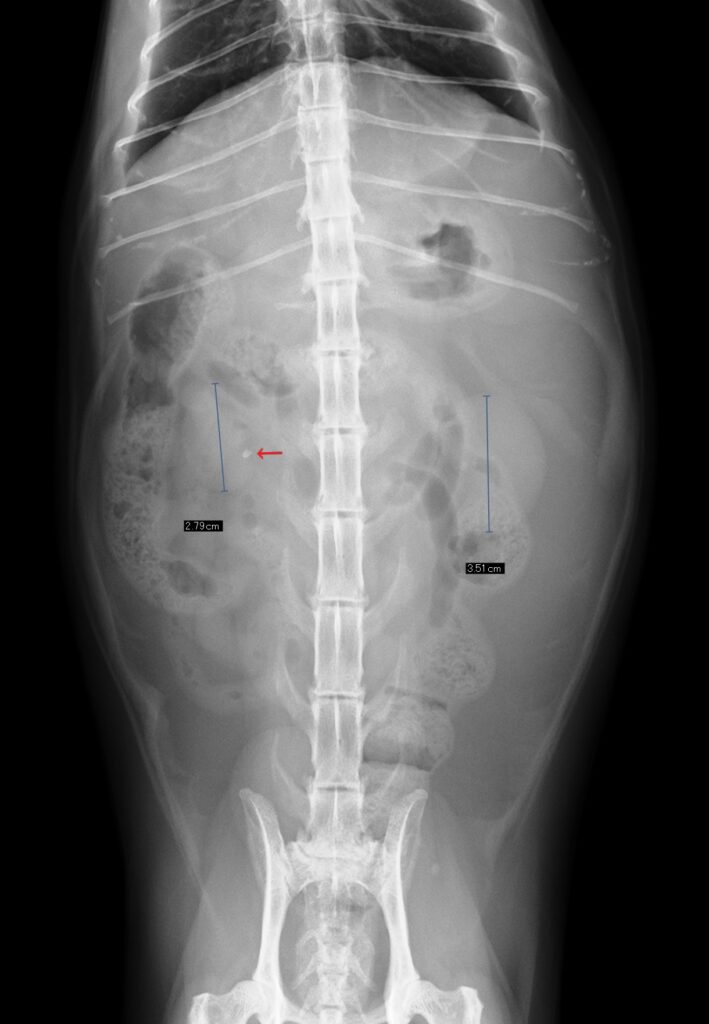

下の画像、左は健康なネコちゃん、右は慢性腎臓病のネコちゃんのレントゲンです。

右側の写真では腎臓の萎縮がみられます。また腎結石(矢印)もみられます。